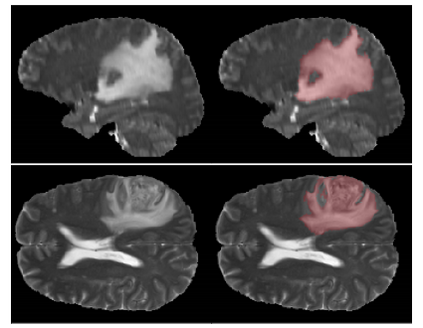

Deep learning motivated by convolutional neural networks has been highly successful in a range of medical imaging problems like image classification, image segmentation, image synthesis etc. However for validation and interpretability, not only do we need the predictions made by the model but also how confident it is while making those predictions. This is important in safety critical applications for the people to accept it. In this work, we used an encoder decoder architecture based on variational inference techniques for segmenting brain tumour images. We evaluate our work on the publicly available BRATS dataset using Dice Similarity Coefficient (DSC) and Intersection Over Union (IOU) as the evaluation metrics. Our model is able to segment brain tumours while taking into account both aleatoric uncertainty and epistemic uncertainty in a principled bayesian manner.